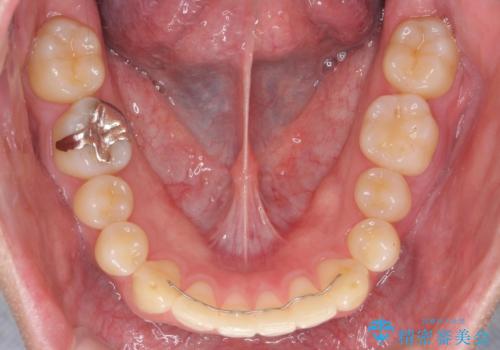

矯正後8年目になりますが、並びも綺麗に保持でき、また上下の歯がさらにしっかり咬んできているのがわかります。

下は歯につけるタイプのワイヤーを貼っています。

上は取り外し式の装置を就寝時使っていただいています。

さしたる問題もなく、半年~1年に一度のメインテナンスにお越しになっている患者様です。保定装置については、慣れれば習慣化するためさほど負担ではありません。

矯正をしなくても起こる下の前歯のがたつきも予防でき、若々しい歯並びを維持することができます。